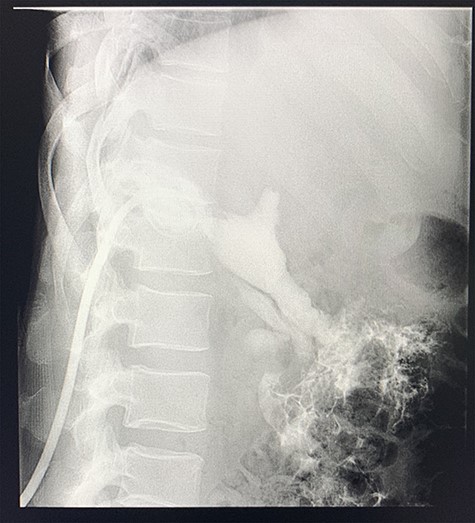

A computed tomography (CT) scan of the abdomen revealed an enlarged, thickened gallbladder with multiple stones, communicating with an intrahepatic collection in segment 4 measuring 116 × 80 mm, with an associated air fluid level and air locules (Fig. 1). There was an apparent fistulous tract to the hepatic flexure of the colon, another large collection in segment 6 (97 × 96 mm) as well as other smaller collections (Figs 2 and 3).

Coronal view of oral and intravenous contrasted CT scan of the abdomen demonstrating features of cholecystitis with fistulous communication with the hepatic flexure of the colon with associated pneumobilia.